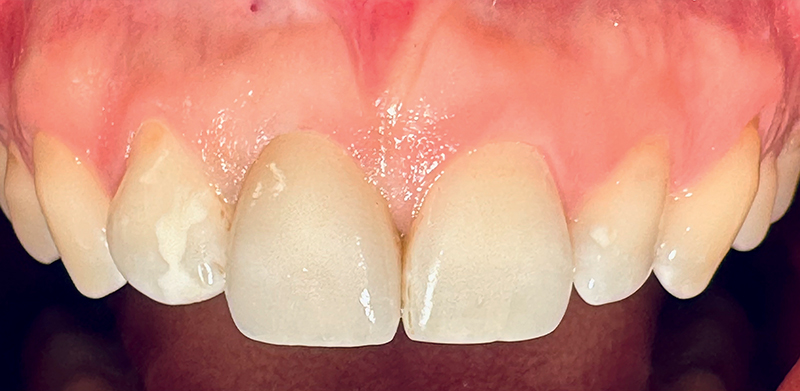

Fig. 15 (caso 3) - Quadro clinico occlusale 5 anni dopo l'impianto. Conservazione della cresta alveolare

Caso 3: Un paziente maschio subiva un trauma durante l'infanzia e si presentava con una fistola associata al dente 11 e un difetto della cresta alveolare vestibolare. Il paziente era sottoposto a posizionamento immediato di un impianto SDS. In questo caso, l'aumento veniva combinato con il prelievo di tessuto connettivo subepiteliale (SCTG) dal palato, attraverso una singola incisione, tunnellizzazione buccale e inserimento dell’innesto. I successivi appuntamenti di follow-up rivelavano il successo della preservazione della cresta alveolare vestibolare, e della guarigione dei tessuti molli attorno all'impianto. L'osteointegrazione avveniva senza problemi e si poteva iniziare la pianificazione della corona definitiva. Questo caso era seguito per 5 anni e anche dopo questo periodo il contorno alveolare era estremamente soddisfacente. La guarigione e la gestione dei tessuti molli erano adeguate, suggerendo come l'applicazione dell'innesto di tessuto connettivo abbia contribuito positivamente al risultato estetico (Fig. 11-17).